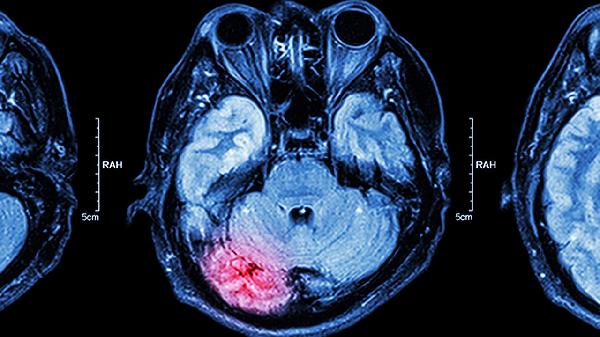

幽門管癌的癥狀主要有上腹疼痛、嘔吐、體重下降、消化道出血、腹部腫塊等。幽門管癌是胃癌的一種特殊類型,通常發(fā)生在胃的幽門部位,早期癥狀可能不明顯,隨著病情發(fā)展,癥狀會(huì)逐漸加重。